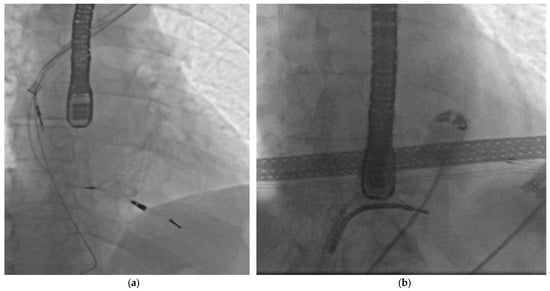

Transvenous Lead Extraction Complicated by Lead Breakage: A Predictive Model Based on Analysis of the EXTRACT Registry

Background: The lead breakage (LB) during transvenous lead extraction (TLE) increases procedural complexity, increases the risk of complications, and decreases procedural efficiency. This study aimed to identify protective and risk factors for the breakage of cardiac electronic device leads during extraction. Methods: Data were sourced from the EXTRACT prospective registry for TLE procedures conducted between January 2016 and June 2025. A total of 702 consecutive TLE procedures involving 1375 leads were enrolled. Multivariate logistic regression was used to identify independent protective and risk factors and develop a model to predict the occurrence of LB during TLE. Results: In the analysed group, 56 (7.98%) of 702 TLE procedures were disrupted by the breakage of at least one lead. The model showed a lower lead breakage rate in procedures when an atrial lead was simultaneously extracted, a locking stylet was used, and when the procedure was conducted in older patients or those who had undergone prior cardiac surgery. Higher risk of LB was proven in the following cases: the extraction of leads implanted a long time ago; the extraction of VDD-type leads; the extraction of abandoned leads; extraction during a prolonged procedure. Occurrence of lead breakage may lead to pericardial effusion requiring intervention, acute kidney injury, or leaving remnants of the leads. Conclusions: Lead breakage is an underestimated procedural difficulty that can occur during transvenous lead extraction. In this study, several clinical and procedural variables were independently associated with lead breakage. Abandoned leads, VDD leads, and prolonged procedure time were associated with increased risk. In contrast, older age, use of a locking stylet, atrial lead extraction, prior cardiac surgery, and later year of implantation demonstrated independent protective associations. Full article